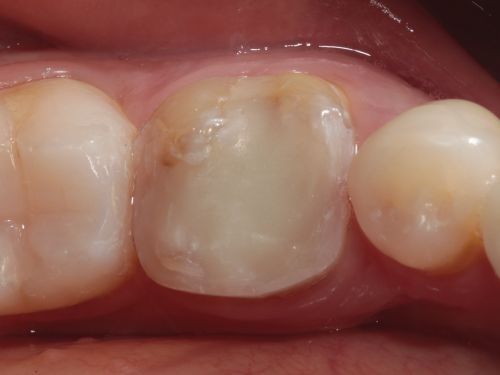

A 35-year-old male presented to the clinic to replace some inadequate restorations, one of which was for the lower right first molar (Fig. 1). For this tooth, the molar was restored with composite resin using the direct technique. The operative field was isolated, the old restoration was removed, and surface hybridization was completed using Futurabond U universal adhesive from Voco (Fig. 2). After placing a sectional matrix and a spacer ring, the composite resin (Voco’s GrandioSO 4U, shade A2) was placed in the proximal box with a thickness less than 4 mm, which is the maximum recommended thickness for the chosen material (Fig. 3). Additional increments of composite resin were applied to complete the anatomical stratification. The final morphology was sculpted, followed by light-curing to ensure complete polymerization (Fig. 4). The rubber dam was removed (Fig. 5), and the occlusion was adjusted using a finishing carbide bur with 12 blades (Fig. 6). Finishing and polishing was completed, with the final result shown in the Figures 7 and 8.